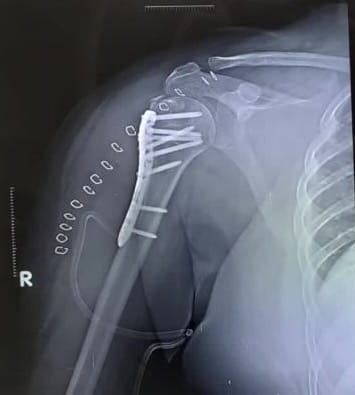

These fractures are another common type of fracture encountered in elderly agents and involves the ball of the upper arm (also known as the head or neck of humerus)

Cause of injuries:

Fall at the individual's residence, usually involving a fall on the outstretched hand or on the side of the shoulder resulting in direct blow to the upper end of the humerus. Other causes could include high velocity injuries following road traffic accident injuries.

The severity of the fractures depends on the force of impact and the bone strength.

Preferred treatment option:

• Type of treatment mainly depends on factors such as severity of the fracture/ fractures, (simple fracture or multiple fragment fractures), cracks extending into the joint. Depending on these factors:

• Non-operative management for fractures that are simple and the cracks DO NOT EXTEND into the joint surface. This treatment follows a principle of immobilisation of the simple fracture with the help of a POP cast and use of a sling to support the injured shoulder for a period of 2-4 weeks depending on the severity of the fracture and bone quality.

• Surgical stabilisation using plates and screws (under ultrasound guided regional Anesthesia- ‘wide awake surgery’) are reserved for fractures that comprise of multiple fragments which have cracked into the joint surface.

Shoulder Replacement (under ultrasound guided regional Anesthesia ‘wide awake surgery’) is reserved for individuals whose fractures are too severe and non-correctable by surgeries using plates & screws. Shoulder replacement surgery for such fractures maybe total shoulder replacement (when the shoulder fracture involves cracks to the ball as well as the socket of shoulder joint) or partial shoulder replacement (where only the shattered ball of the ball & socket joint is replaced without disturbing the normal anatomy of the socket of shoulder joint).

Recovery time:

In individuals who have been treated non operatively the shoulder joint will be immobilised for a period of 4-6 weeks before starting him/ her on gradual shoulder movement exercises and gradually by the 8th to 12th week, the individual is started on shoulder strengthening exercises before being lower to resume all daily activities.

In individuals whose shoulder fractures are treated surgically (surgical fixation of fracture as well as shoulder joint replacement) movement of the injured shoulder is started within 24 hours and the patient is allowed to carry out all his/ her daily activities within 2 weeks.